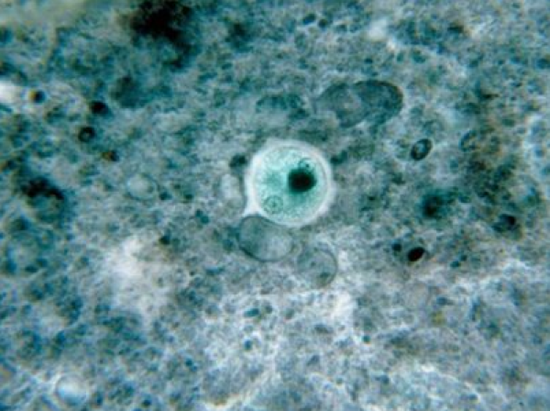

少年感染食脑虫死亡,图为阿米巴原食脑虫

食脑虫又称“吃脑寄生虫”,会引发阿米巴痢疾、肝脓肿、脑膜脑炎、角膜炎、口腔感染和皮肤损伤等。人在江河湖塘中游泳或用疫水洗鼻时,食脑虫会进入鼻腔,其后上行入脑,侵入中枢神经系统。对人体的危害性十分大。

报道指出,这种听上去骇人万分的“食脑虫”虽然只是单细胞生物,但却能通过鼻孔进入中枢神经系统,感染大脑,最终导致被感染者脑死亡。虽然在过去53年内只有133起“食脑虫”感染记录在案,但一旦感染,这种病菌非常致命,此前仅有3人在感染“食脑虫”后存活下来。